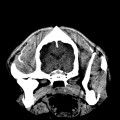

CT - lebka